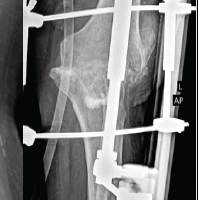

A 28-year-old woman arrived with a 20-year history of gradually increasing pain, swelling, and deformity of the left hemibody, particularly the lower limb, accompanied by functional scoliosis with right-side convexity. Symptoms first appeared in childhood. Upon examination, notable hypertrophy and joint stiffness were observed in the left lower limb (Fig. 1), with a 4.5 cm length discrepancy in the left lower limb, left-sided genu valgum, foot varus, and equinus deformity, along with hyperpigmentation and a scar over the left ankle. The skin over the lumbar region exhibited hyperpigmentation with a 4.5 cm soft tissue swelling at the L3 level (Fig. 2) and nodular thickening over the medial malleolus. Hip and knee fixed flexion deformities measured 25° and 90°, respectively. Digital radiographs and computed tomography (CT) scans demonstrated diffuse cortical thickening and hyperostosis affecting the pelvis, femur, tibia, talus, calcaneus, and tarsal bones of the left side, with partial joint fusion and medullary cavity obliteration, characteristic of “candle wax dripping” [4] (Fig. 3-7).

Melorheostosis, first designated in 1922 by Leri and Joanny [6], remains an exceedingly rare condition that can manifest at any age with equal prevalence among both sexes. Its etiology remains unclear, though hypotheses include defects in mesenchymal cell differentiation (notably mutations in LEMD3)[7], vascular anomalies, and inflammatory processes, though none have been definitively confirmed. In osteoblastic regulation, research by Kim J-E has indicated that adhesion proteins, particularly the transforming growth factor ß-induced gene product, may be downregulated. This occurrence might lead to hyperostosis and associated soft tissue abnormalities [8]. One conceivable explanation is a loss-of-function mutation in the LEMD3 gene (12q12–12q14.3), which is essential for bone morphogenic protein and tumor growth factor-β pathways. These genetic links emphasize the need for further research to clarify causative mechanisms and explore the potential of gene therapy in disease management. Manifestations vary widely, from asymptomatic cases to severe pain and deformity. Symptoms usually develop insidiously, presenting with pain, stiffness, skin changes, and skeletal deformities. Our patient reported pain beginning at age eight, progressing gradually with worsening deformity. Lesion distribution ranges from monomelic (affecting one limb, the most common form) to hemimelic (involving both upper and lower limbs). It may be monostotic (impacting a single bone) or polyostotic (affecting multiple bones). In this case, the disease presented in a hemimelic, polyostotic form, an atypical occurrence. While melorheostosis predominantly affects long bones, axial skeletal involvement is rare. In addition, it has been linked to neoplasms, such as malignant fibrous histiocytoma, osteogenic sarcoma, and dermoid tumors. Differential diagnoses include osteopathic striata, parosteal osteosarcoma, osteopoikilosis, myositis ossificans, and osteoma, particularly in forme fruste cases. In this patient, the diagnosis was straightforward based on clinical presentation, radiographic findings, CT imaging, and histological features. Diagnosis relies primarily on radiographic findings, with classic “dripping candle wax” appearance distinguished by cortical hyperostosis, increased bone thickness, linear density extending into cancellous bone [9]. In this case, radiographic evidence clearly supported the diagnosis. Laboratory investigations were unremarkable, a hallmark of this condition. Histopathological findings generally lack specificity, with a heterogeneous mix of mature and immature bone forming a dense structure with elevated trabecular bone. While osteoclastic activity has been uncommon, mild osteoblastic proliferation is frequently observed, aligning with findings in this case. Treatment is predominantly symptomatic, with most patients undergoing non-operative management. Surgery is reserved for cases involving contractures and severe deformities, including tendon lengthening, osteotomies, excision of hyperostotic bone, or, in extreme cases, amputation [10]. Our patient was prescribed aceclofenac 100 mg twice daily, which provided symptom relief. Melorheostosis remains an exceedingly rare disorder marked by linear hyperostosis laterally the cortical bone. On the clinical level, it manifests localized pain and deformity, and the diagnosis is determined through combining of imaging and clinical assessment. No definitive treatment exists, as well as management focuses primarily on symptomatic relief.